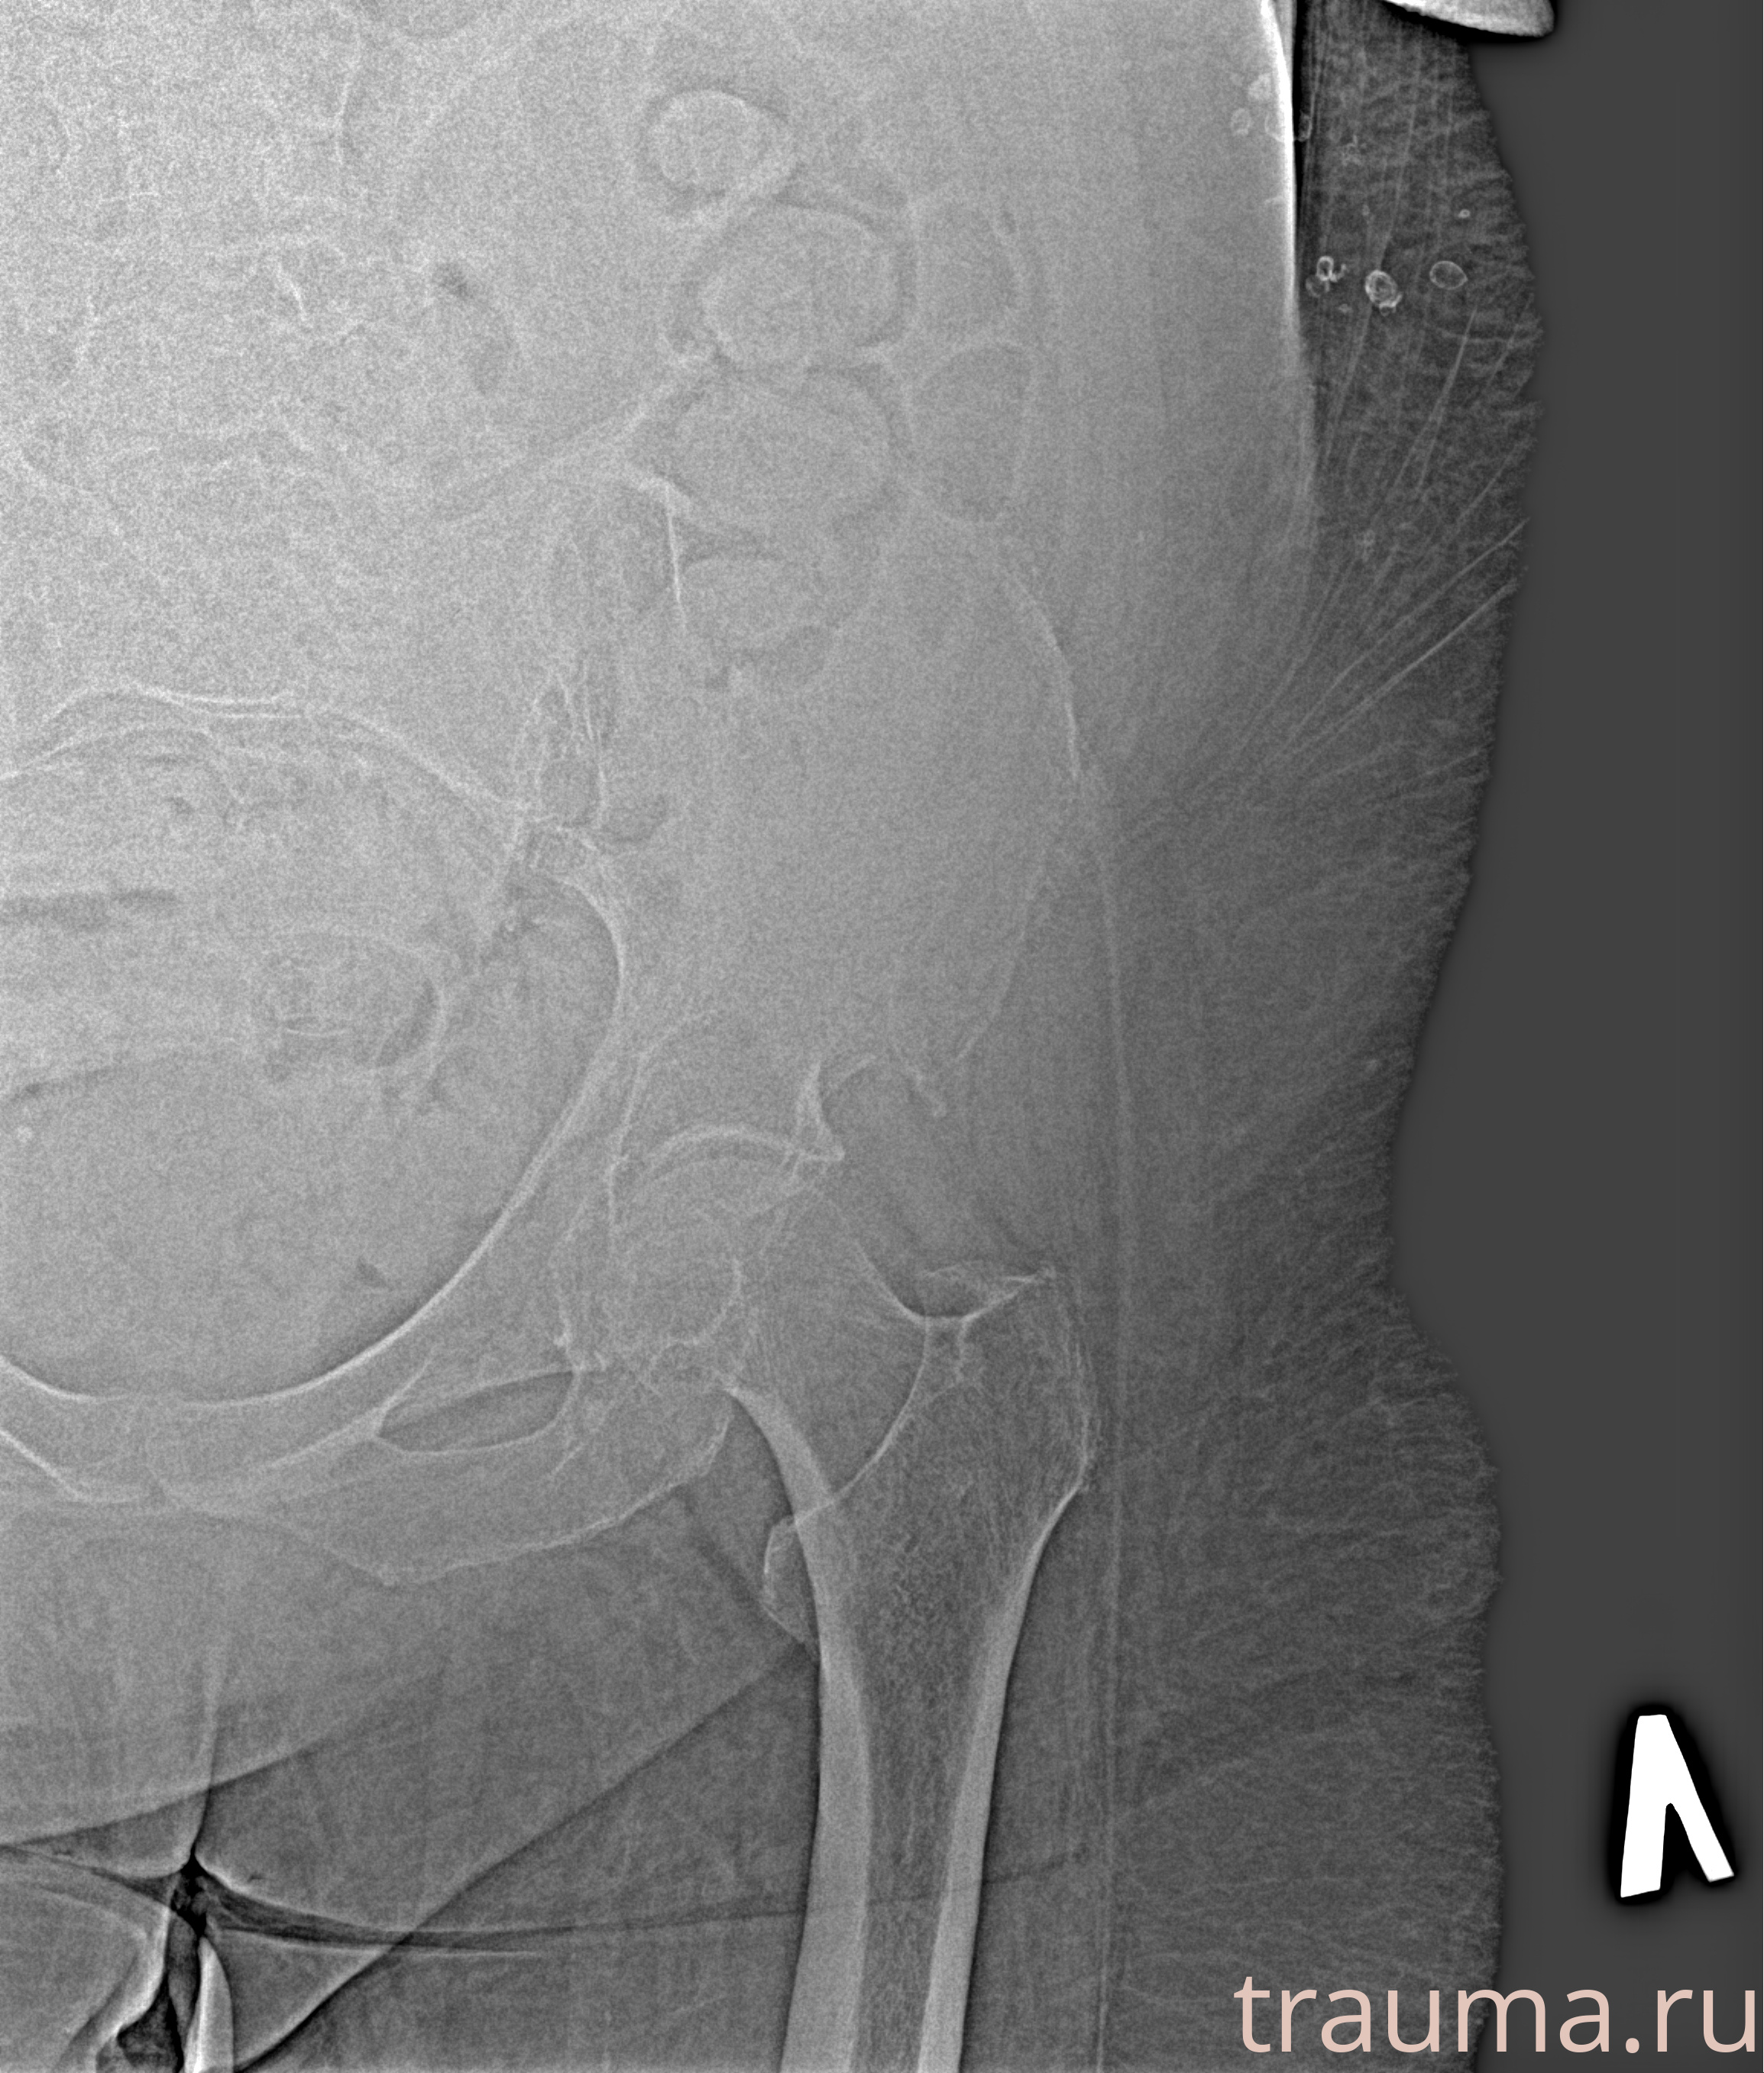

Рентген на дому: по вашему адресу приезжает врач-рентгенолог, травматолог-ортопед с мобильным рентгеновским аппаратом, проводит диагностику травмы или заболевания, делает необходимые рентгенограммы, дает рекомендации по дальнейшему лечению. Получить качественные снимки в домашних условиях возможно благодаря уникальной методике, разработанной МосРентген Центром для института  Склифосовского